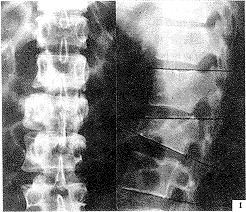

, http://www.100md.com 3.2.1 骨折椎平面 间接减压效果T12、L1骨折优于L2骨折。这可能与T12、 L1正常生理状态下有轻度后凸,在恢复脊柱前凸过程中,后纵韧带及椎间盘纤维环张力较大,使骨块复位应力增强,而L2是后凸与腰椎前凸过渡椎,纵向韧带张应力增大不明显有关。根据间接复位能力不同这一特点,后期我们对L2骨折术前存在严重椎管入侵(>50%)者,在实施复位固定同时,作经椎弓根侧前方减压,使术后椎管腔达到足够的减压范围,见图1~3。

图1 L2爆裂型骨折术前X线片